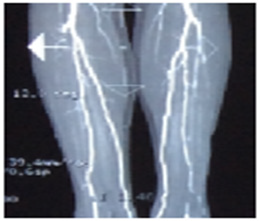

Case 1: The arteria peroneal of a 76-year-old man was blocked as shown in Figure 2. Doctor suggested him to take an operation after the other two vascular being blocked. He asked us to help. We gave him 40 minutes MRT in the afternoon. At that night, as he was sleeping, he felt terrible itch on shank and foot. And he thought why there were so many mosquitoes this night. Suddenly, he understood that it was not a mosquito, but the blood was flowing though the shank and foot. Nevertheless, we gave him two days MRT again (40 minutes/day) and suggested him to take another test. He said: “no need, I can feel it is very well”. Now he is 90 years old and can walk 500m by push a wheelchair.